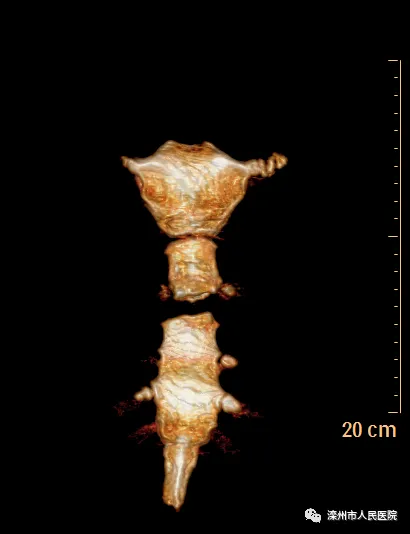

術(shù)后影像

本次手術(shù)改變以往行鋼絲縫合的方法,改用環(huán)抱式胸骨固定器,既減少了組織分離造成的損傷,又避免了胸骨內(nèi)側(cè)穿鋼絲的意外損傷,而且固定效果滿意。